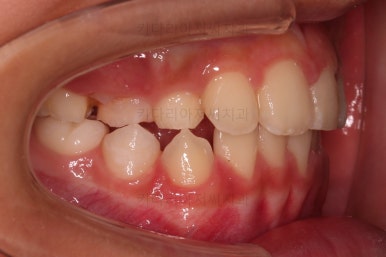

CASE 1.

나이 : 9세

총 치료기간 : 3개월

초진 시 얼굴사진인데요.

우선 중요한 건 진짜 주걱턱이냐 아니냐가 중요해요.

이번 환자분은 다행히 뼈의 문제는 없는 것으로 판단이 되었는데요.

그래서 이번 환자분도 뼈의 문제는 없지만 앞니가 거꾸로 물리는 건 개선해주자고 했죠.

바로 전후 비교사진 올립니다.

골격의 문제가 없었고 골격에 대한 치료가 아니었지만 얼굴 모습도 약간의변화가 있죠?

함몰감이 약간 있던 윗입술 부분이 볼륨감이 생기면서 자연스러운 아이얼굴 비율이 되었어요.

치열도 자연스럽게 예뻐졌네요.

3개월만에요😄